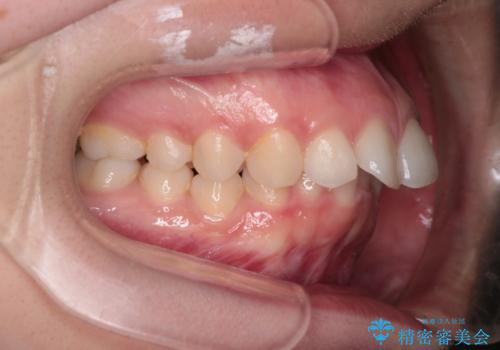

【インビザライン】前歯を引っ込めたい

- 前歯が出ていることを主訴に来院された患者様です。

抜歯を希望されなかっため、臼歯部の遠心移動やIPRを行い配列を行っています。

抜歯をしていない矯正となるため、口元に大きな変化は認められません。